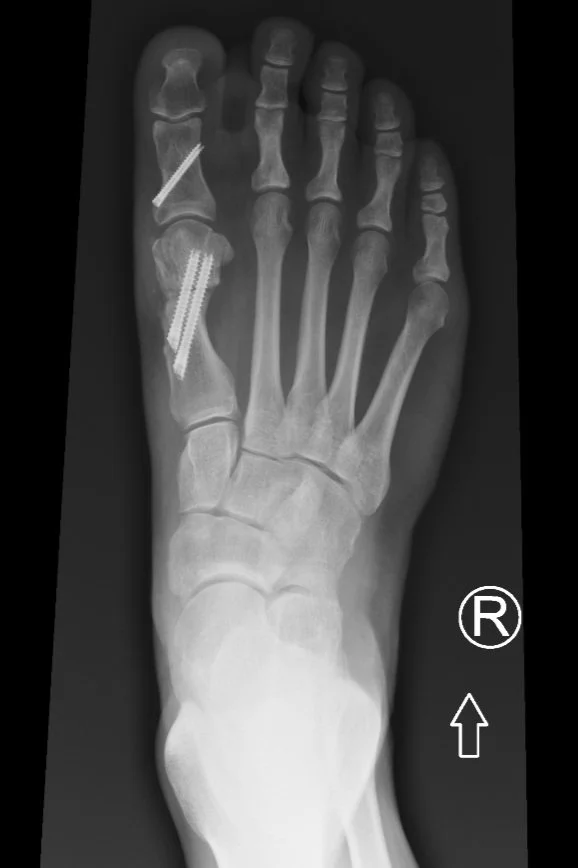

Bunion Correction with Scarf and Akin Osteotomy California Bunion Correction Options Types of bunion surgery include removing the whole bunion, realigning the joint, removing areas of damage in the toe joint, and more. This involves cutting the first metatarsal bone and the big toe bone, repositioning them to correct the alignment On the other hand, lapiplasty provides a comprehensive solution to bunion correction by realigning the entire bone structure in three. Bunion Correction Options.